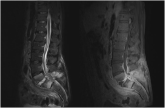

ArticleEvaluation of Spinal Epidural AbscessAuthor:Mark A. Palumbo, MDPublish date: November 5, 2015Read More